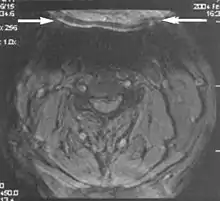

Motion artifacts

A motion artifact is one of the most common artifacts in MR imaging.[2] Motion can cause either ghost images or diffuse image noise in the phase-encoding direction. The reason for mainly affecting data sampling in the phase-encoding direction is the significant difference in the time of acquisition in the frequency- and phase-encoding directions.[1] Frequency-encoding sampling in all the rows of the matrix (128, 256 or 512) takes place during a single echo (milliseconds). Phase-encoded sampling takes several seconds, or even minutes, owing to the collection of all the k-space lines to enable Fourier analysis. Major physiological movements are of millisecond to seconds duration and thus too slow to affect frequency-encoded sampling, but they have a pronounced effect in the phase-encoding direction. Periodic movements such as cardiac movement and blood vessel or CSF pulsation cause ghost images, while non-periodic movement causes diffuse image noise (Fig. 1). Ghost image intensity increases with amplitude of movement and the signal intensity from the moving tissue. Several methods can be used to reduce motion artifacts, including patient immobilisation, cardiac and respiratory gating, signal suppression of the tissue causing the artifact, choosing the shorter dimension of the matrix as the phase-encoding direction, view-ordering or phase-reordering methods and swapping phase and frequency-encoding directions to move the artifact out of the field of interest.[1]